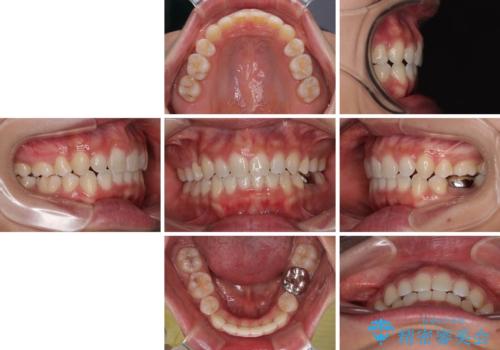

途中出産や育児があり、治療期間長くなってしまいましたが、ストレスなく唇が閉じられるような口元に仕上げることができました。